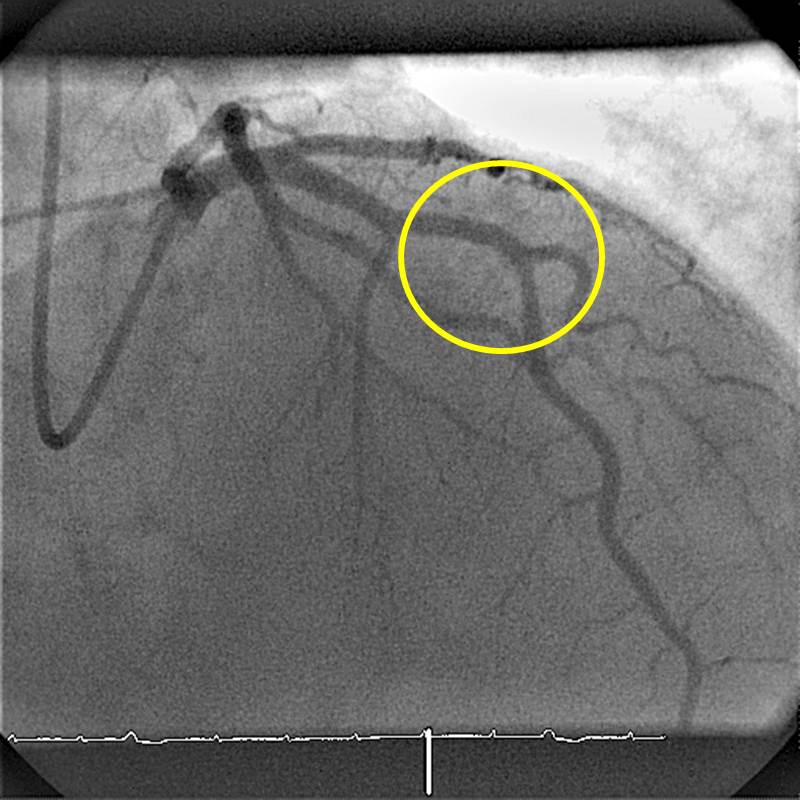

RIVA Stentimplantation

Aufdehnung der Stenose durch Implantation eines Stents, der mit einem Ballon in der Stenose entfaltet wird. Der Ballon ist in dem Bild dunkel gefärbt.

Der Ballonkatheter wird nach Entleeren wieder herausgezogen und der Stent bleibt unverändert in der Arterienwand, sodass der Blutfluss im Bereich der Stenose wieder normalisiert ist.

RIVA nach Stent

Darstellung der Vorderwandherzkranzarterie nach Stentimplantation. Die Stenose ist nicht mehr nachweisbar (Markierung durch gelben Kreis).